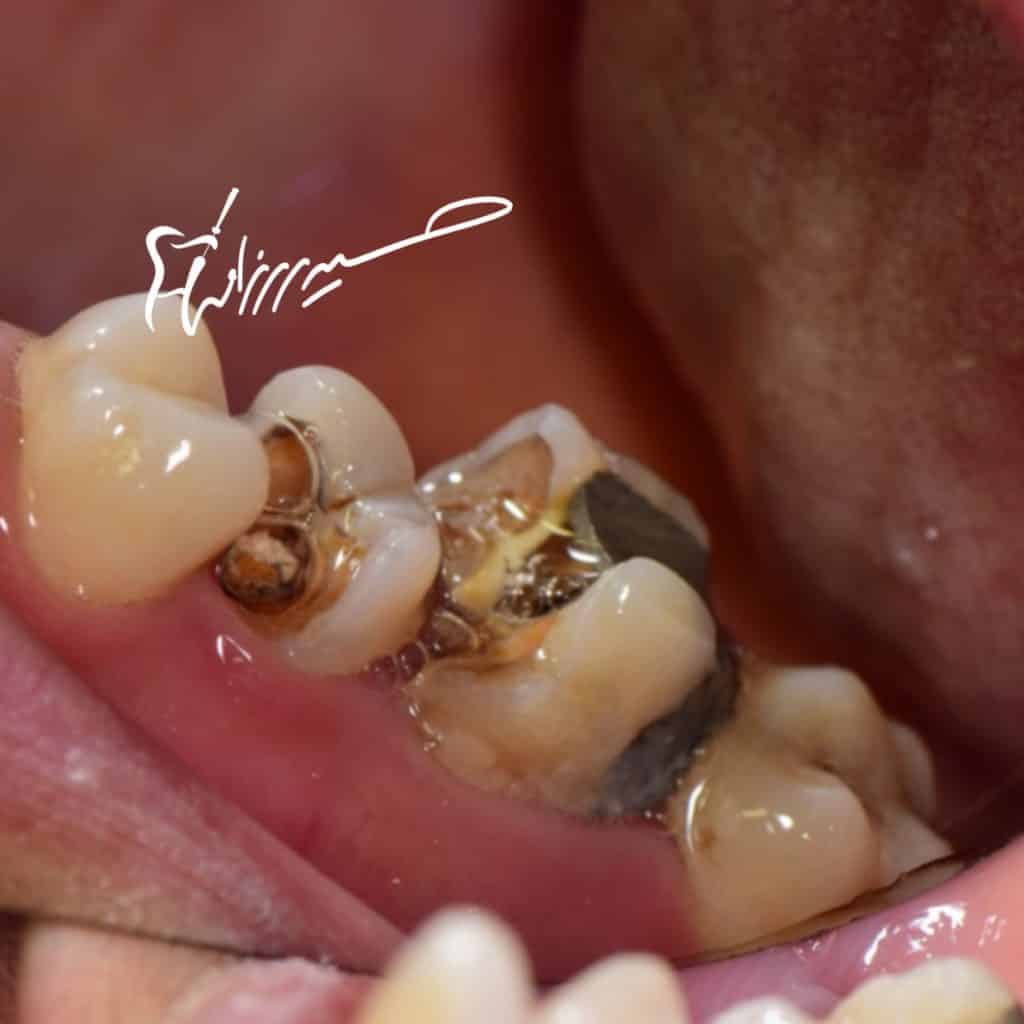

Bad RCT need re treatment

deep margin must elevate

destructive structures and there is no feruule

so adhesive options are the best